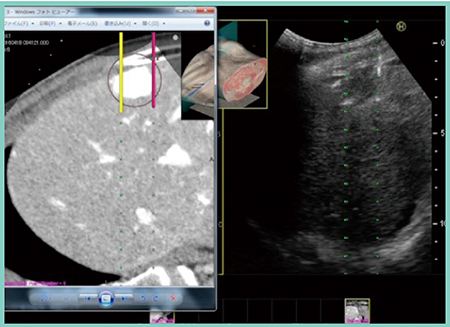

3.平行穿刺法を応用した3本穿刺法:2+1法

2つのプローブを用いて2本の平行穿刺と1本穿刺を組み合わせて行う3本穿刺を「2+1法」と命名した。この時,日立製作所社製の超音波診断装置に搭載されている“Real-time Biplane”機能を用いることで,2つのプローブの画像を並列表示可能にする(図1 左)。実際に穿刺を行ってみたところ,3本穿刺に要した時間は約1分30秒で(図1),焼灼が不十分なところはリアルタイムに針の位置補正も可能であり,治療後のCT画像では十分なマージンを取って焼灼できていることが確認できた。

図1 2+1法における実際の穿刺